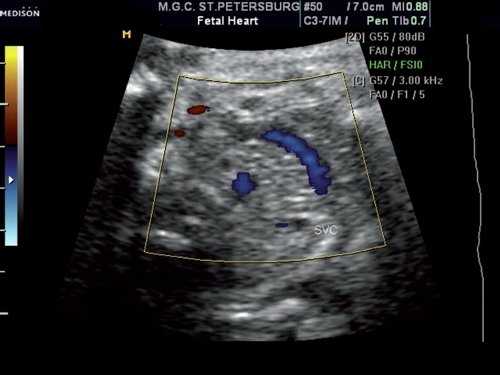

При исследовании в режиме ЦДК сохранялось направление тока крови слева направо (рис. 3), при исследовании в режиме импульсного допплера спектр кровотока в этом сосуде соответствовал двухфазному спектру кровотока в венах, располагающихся близко к сердцу (рис. 4). Учитывая направление и спектр тока крови в сосуде, был сделан вывод, что данный сосуд представляет собой левую безымянную (плечеголовную) вену.

Рис. 3. Поперечное сечение грудной клетки плода выше среза через три сосуда. Режим ЦДК. В сосуде регистрируется направление тока крови слева направо.